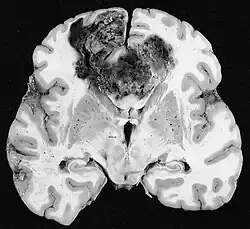

Glioblastome

Die sowohl häufigsten als auch bösartigsten Gliazelltumoren sind Glioblastome. Sie bestehen aus einer heterogenen Masse schlecht differenzierter Astrozytomzellen hauptsächlich bei Erwachsenen. Normalerweise treten sie in den Gehirnhälften auf, seltener am Hirnstamm oder Rückenmark. Außer in sehr seltenen Fällen dehnen sie sich wie alle Hirntumoren nicht über die Strukturen des Zentralnervensystems hinaus aus.[22]

Das Glioblastom kann sich aus einem diffusen (II. Grades) oder einem anaplastischen Astrozytom (III. Grades) entwickeln. In letzterem Fall wird es als sekundär bezeichnet. Tritt es jedoch ohne Vorstadien oder ohne Anzeichen einer früheren Malignität auf, bezeichnet man es als primär. Glioblastome werden mittels Operationen, Bestrahlung und Chemotherapie behandelt. Sie sind schwer zu heilen und es gibt nur wenige Überlebensfälle von über drei Jahren.[23]

Im Tumorgewebe ist im Allgemeinen der größere Anteil der Kontrastverstärkung auf die besondere Blut-Tumor-Schranke zurückzuführen, die den Durchgang von Iod (CT) und Gadolinium (MRT) in den intratumoralen extravaskulären Interstitialraum ermöglicht. Dadurch steigt das Signal (Dichte oder Intensität) des Tumors. Es sollte jedoch darauf geachtet werden, dass die Kontrastverstärkung die Neoplasie von Periwundödemen nicht mit Sicherheit abgrenzt. Tatsächlich zeigt der anatomisch-pathologische Befund bei malignen infiltrierenden Gliomen Tumorgewebe, wie zum Beispiel beim Glioblastom und anaplastischem Astrozytom, auch jenseits des vasogenen Ödems, das durch die Zerstörung der Blut-Hirn-Schranke durch den Tumor verursacht wird. Letzterer klinischer Zustand ist durch diagnostische Bildgebung schlecht nachweisbar.[5][6]